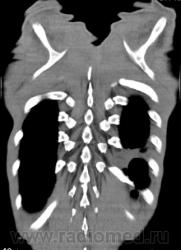

На фоне консолидации полость без содержимого. Может быть всё что угодно, что сопровождается деструкцией. Нужны ещё томограммы в лёгочном окне.

Изображения выставлены все. Ваше мнение уважаемые коллеги?

Это КТ 2-летней давности и попало оно мне в руки, после недавнего прохождения контроля пациентом, когда мы стали перед вопросом о специфическом / не специфическом процессе.

Тогда, пациента 2 месяца лечили от пневмонии, лечили интенсивности, стационарно, в серьёзном учреждении.

В этом году пациент взят на "контроль"

Прямая и "семерка".

Предположу аспергиллез